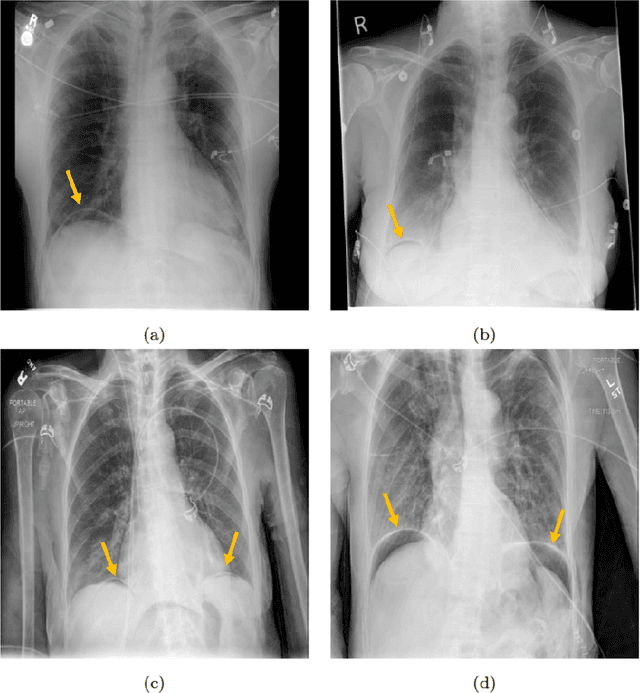

Abstract:Background: Deep learning has great potential to assist with detecting and triaging critical findings such as pneumoperitoneum on medical images. To be clinically useful, the performance of this technology still needs to be validated for generalizability across different types of imaging systems. Materials and Methods: This retrospective study included 1,287 chest X-ray images of patients who underwent initial chest radiography at 13 different hospitals between 2011 and 2019. The chest X-ray images were labelled independently by four radiologist experts as positive or negative for pneumoperitoneum. State-of-the-art deep learning models (ResNet101, InceptionV3, DenseNet161, and ResNeXt101) were trained on a subset of this dataset, and the automated classification performance was evaluated on the rest of the dataset by measuring the AUC, sensitivity, and specificity for each model. Furthermore, the generalizability of these deep learning models was assessed by stratifying the test dataset according to the type of the utilized imaging systems. Results: All deep learning models performed well for identifying radiographs with pneumoperitoneum, while DenseNet161 achieved the highest AUC of 95.7%, Specificity of 89.9%, and Sensitivity of 91.6%. DenseNet161 model was able to accurately classify radiographs from different imaging systems (Accuracy: 90.8%), while it was trained on images captured from a specific imaging system from a single institution. This result suggests the generalizability of our model for learning salient features in chest X-ray images to detect pneumoperitoneum, independent of the imaging system.